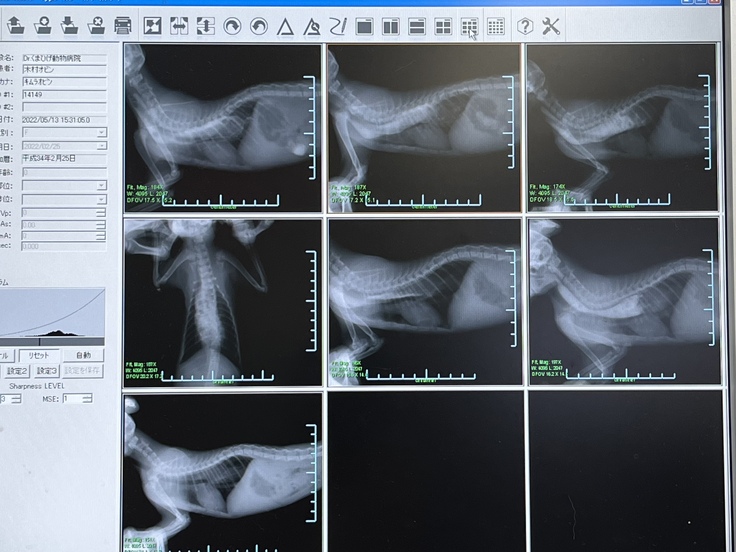

先生は、『通常の嘔吐の様子ではないので、何か原因がありそうだから調べてみましょう』とご提案くださり、その日のうちにバリウムを使用してのX線撮影をしてくださいました。

6月3日、ほぼ1日がかりで検査をしていただき、その時点での先生の診断は【食道狭窄】と、それが原因で2次的に引き起こされた【食道拡張】でした。もちろん食道は大きく拡張しているので、【巨大食道(拡張)】の状態ですが、【巨大食道症】という診断ではなく、そもそも食道が拡張した原因が【食道狭窄】なのだそうです。

バリウム使用してのX線撮影の検査のみであれば通常【巨大食道症】と診断されるそうです。かかりつけ病院の先生が、大きな病院でもっと詳しい検査をした方がいい、と背中を押してくださらなければ【食道狭窄】という診断には辿り着けませんでした。

オビンの内視鏡バルーン拡張術時の画像です。

狭窄部(胃の入口の直前が狭窄)はだいぶ狭くなっていたそうです。

バルーンで裂け出血している食道の壁が痛々しく、狭窄部の狭さに驚きました。